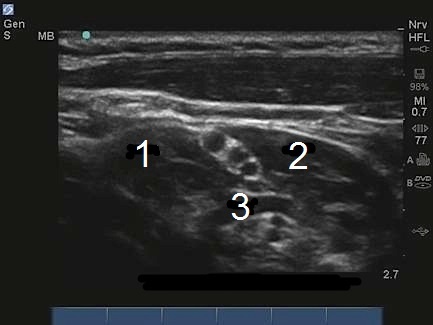

M-Turbo:腕神経叢斜角筋間レベル5

MSM

ASM

動脈